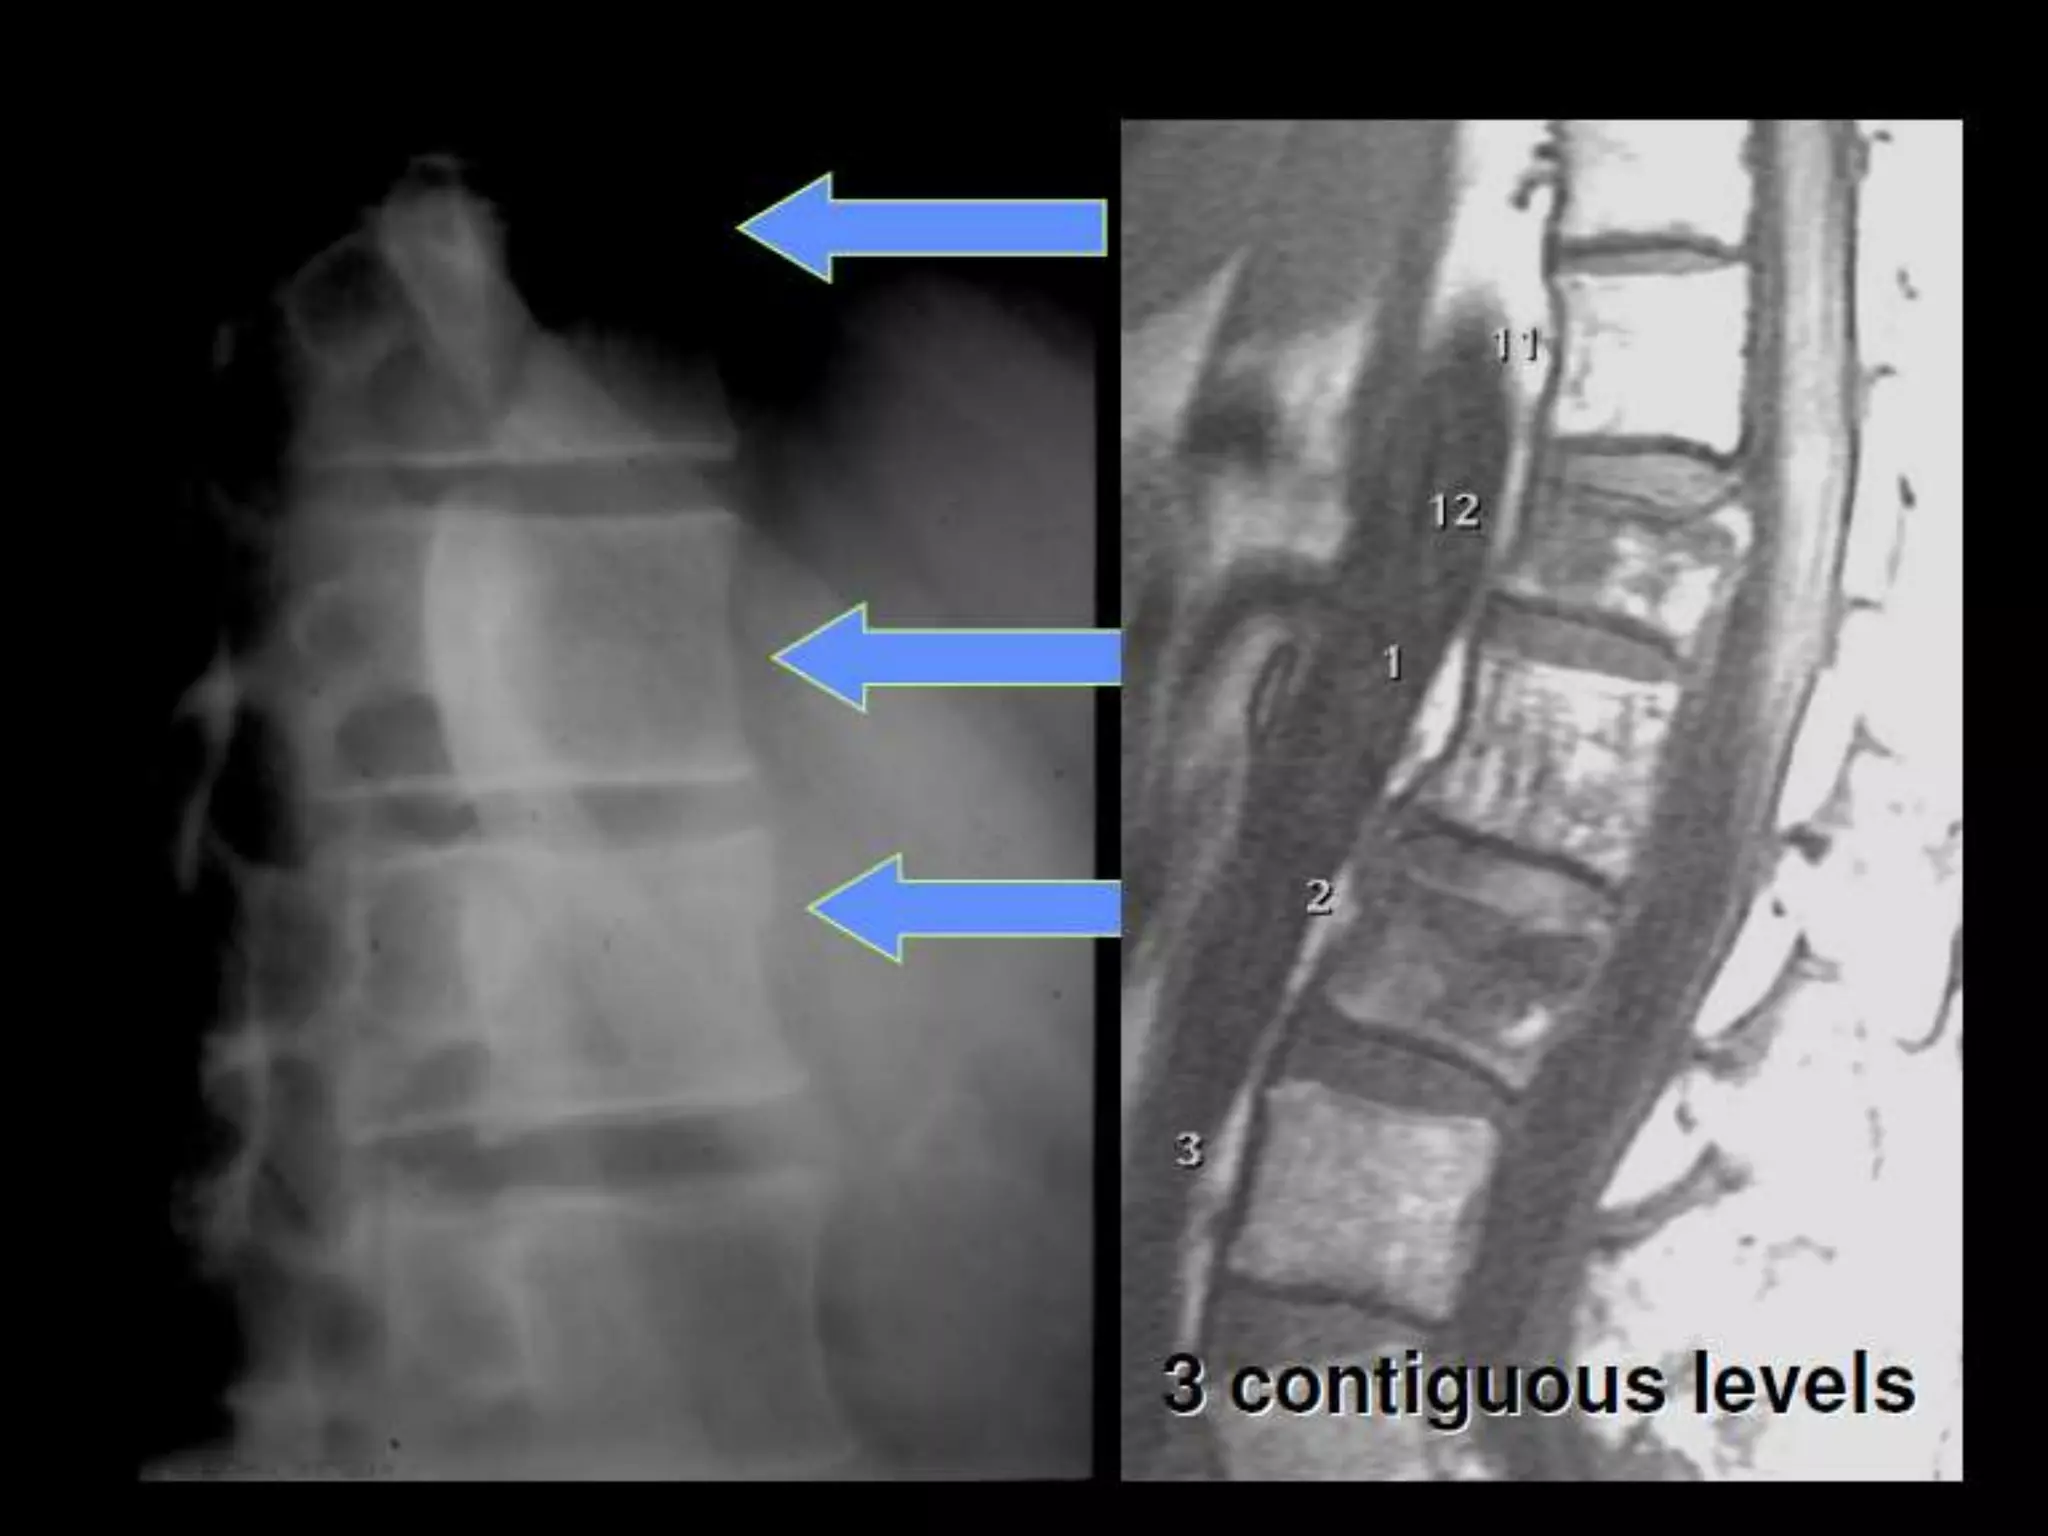

Axial Load

• T-L junction - most common site

of injury

• T-spine - may result in flexion force,

anterior wedge compression or burst

• 43% fx at another level

• 10% non-contiguous: need to survey

whole spine

Coronal T2W image dorso lumbar spine of a 29 yr old male

patient showing burst fracture(arrow) of L3 vertebra.

Axial Load •T-L junction - most common site of injury • T-spine - may result in flexion force, anterior wedge compression or burst • 43% fx at another level • 10% non-contiguous: need to survey whole spine

Coronal T2W imagedorso lumbar spine of a 29 yr old male patient showing burst fracture(arrow) of L3 vertebra.